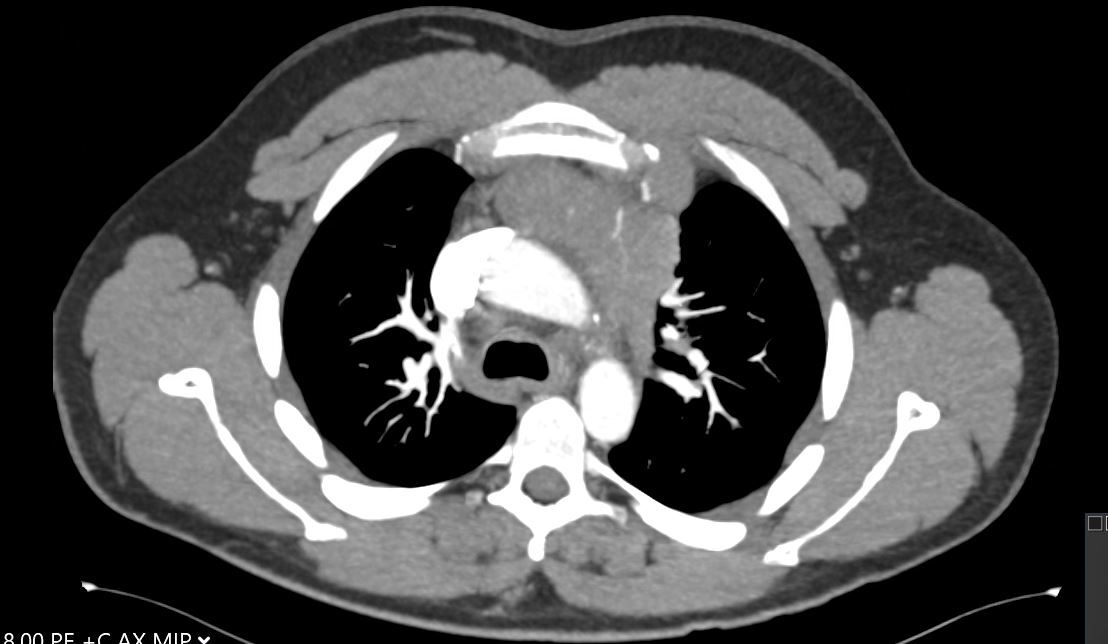

A 30-year-old man presents with dyspnea and is found to have an anterior mediastinal mass, as well as supraclavicular lymphadenopathy; biopsy of the mass is consistent with thymic carcinoma. Imaging shows his anterior mediastinal mass, lung and diaphragmatic lesions consistent with metastatic malignancy, and probable pericardial involvement with small pericardial effusion (Figures 1, 2, 3, and 4).

Fig. 2: CT image showing large mediastinal mass found to be thymic carcinoma. -